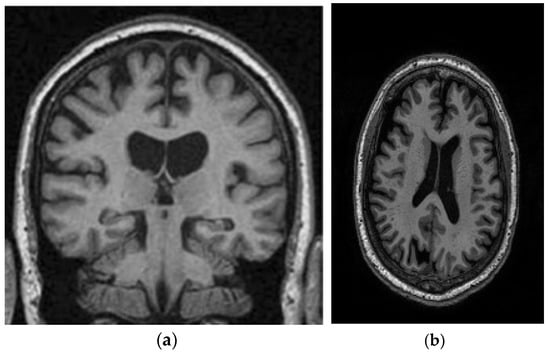

A range of influences affect the onset of Alzheimer’s disease, among them lifestyle choices, cardiovascular health, head trauma, age, gender, genetic predispositions, infections, environmental influences, and pre-existing conditions like diabetes, as depicted in Figure 1. In individuals with Alzheimer’s, abnormal protein formations such as amyloid plaques and neurofibrillary tangles develop in and around neurons in specific areas of the brain [29]. These pathological changes lead to the deterioration and damage of brain tissues, as shown in Figure 2 [30].

Figure 2.

The regions of the brain affected by Alzheimer’s disease in MRI images [30].

This study utilizes two distinct datasets, ADNI and MIRIAD, to investigate Alzheimer’s disease, ensuring a diverse range of demographics and imaging modalities. The ADNI dataset, which tracks the early stages of Alzheimer’s, consists of MRI scans, specifically 128 sagittal slices per scan, each formatted as a 256 × 256 matrix. It includes a total of 741 participants, with 314 images from Alzheimer’s patients and 427 from normal controls. The participants represent a wide variety of ages, genders, and ethnic backgrounds, ensuring that the model is robust and can perform well across different populations. The MIRIAD dataset also focuses on Alzheimer’s, containing MRI brain scans from 46 Alzheimer’s patients and 23 normal controls, with follow-up scans taken at intervals ranging from 2 weeks to 2 years [44,45]. Both datasets are sourced from various institutions, introducing variability in the acquisition conditions, which further enhances the model’s robustness and its ability to generalize to real-world scenarios. The inclusion of different ethnic backgrounds, as well as varying patient ages and scan intervals, ensures that the model is adaptable to diverse clinical environments. Figure 8 shows examples of benign and malignant images from these datasets. Table 1 summarizes the key settings and configurations used in the experiments to analyze Alzheimer’s disease using HHO and CNN-based approaches.

Figure 8.

Two sample images from the ADNI and MIRIAD datasets: (a) MIRIAD dataset [46]; (b) slices from the ADNI Dataset [47].